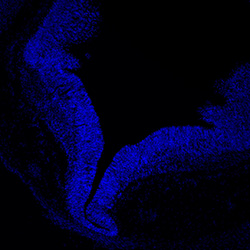

6PCW

DAPI

6PCW human midbrain